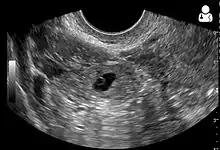

An ultrasound showing a gestational sac with fetal heart in the fallopian tube has a very high specificity of ectopic pregnancy. It involves a long, thin transducer, covered with the conducting gel and a plastic/latex sheath and inserted into the vagina.[32] Transvaginal ultrasonography has a sensitivity of at least 90% for ectopic pregnancy.[5] The diagnostic ultrasonographic finding in ectopic pregnancy is an adnexal mass that moves separately from the ovary. In around 60% of cases, it is an inhomogeneous or a noncystic adnexal mass sometimes known as the "blob sign". It is generally spherical, but a more tubular appearance may be seen in case of hematosalpinx. This sign has been estimated to have a sensitivity of 84% and specificity of 99% in diagnosing ectopic pregnancy.[5] In the study estimating these values, the blob sign had a positive predictive value of 96% and a negative predictive value of 95%.[5] The visualization of an empty extrauterine gestational sac is sometimes known as the "bagel sign", and is present in around 20% of cases.[5] In another 20% of cases, there is visualization of a gestational sac containing a yolk sac or an embryo.[5] Ectopic pregnancies where there is visualization of cardiac activity are sometimes termed "viable ectopic".[5]

A pregnancy not in the uterus[33]